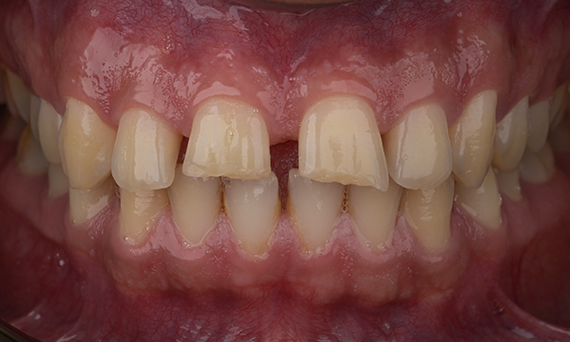

A particular and protracted case of skeletal Class II malocclusion and generalized amelogenesis imperfecta in a teenager was referred for prosthetic rehabilitation. The aim of the treatment was to prepare the remaining tooth structure, remove undercuts, and make room for all-ceramic crowns covering the entire dentine and simulating the lost enamel.

Before: Initial situation prior to orthodontic treatment.

After: Final result, 1 week post-operative.